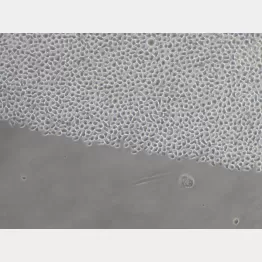

「市販の液体ノリで、白血病の治療に重要な造血幹細胞の大量培養に成功した」――東京大学の中内啓光教授らのこんな研究成果が30日、英科学誌ネイチャー(電子版)に掲載された。

中内教授らは、液体ノリに含まれる成分ポリビニルアルコールが、血液のもとを作る造血幹細胞を最大約1000倍に増殖できることを発見。コンビニで買った液体ノリ「アラビックヤマト」を使ったマウス実験で移植に使えることを確認したという。この方法なら献血のように腕から採取した血液からも必要なだけの造血幹細胞を作ることができる。

将来は、骨髄移植に代わる白血病などの治療を後押しできると期待しているという。